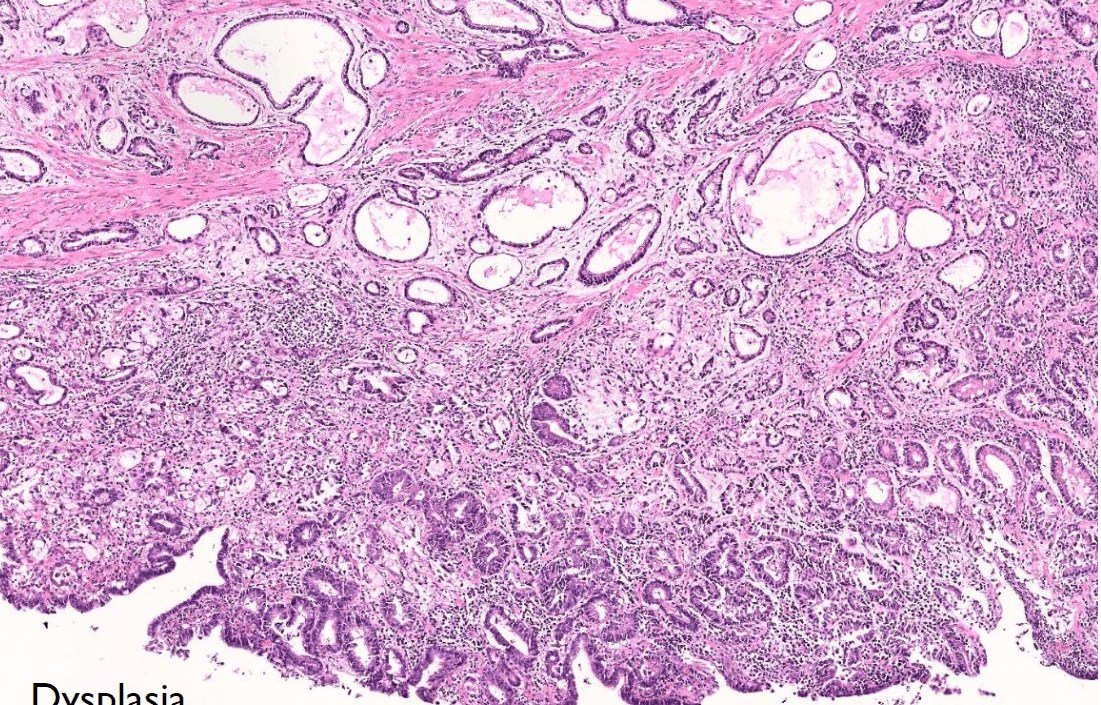

colon cancer